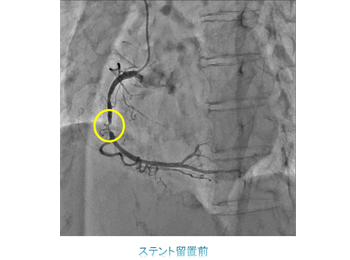

一方治療には、狭くなった冠動脈にステントを留置する冠動脈ステント留置術(PCI)をはじめ、心臓以外の動脈や静脈を拡張させる血管拡張術(PTA)、頻脈性不整脈の原因となる電気回路を遮断させるため、心筋に高周波電流を流して焼灼するアブレーションや、徐脈性不整脈に対するペースメーカー埋込術(PMI)、除細動器のデバイス埋め込み術(ICD)などがあります。

ハイブリット手術室では経皮的大動脈弁置換術(TAVI)、経皮的僧帽弁クリップ術(MitraClip)、左心耳閉鎖術(WATCHMAN)などの構造的心疾患(SHD:Structure Heart Disease)に対するインターベンションをはじめ、大動脈解離や大動脈瘤に対するステントグラフト内挿術(TEVAR、EVAR)、エキシマレーザーを用いたデバイスリード抜去術など、様々な手技を行っています。